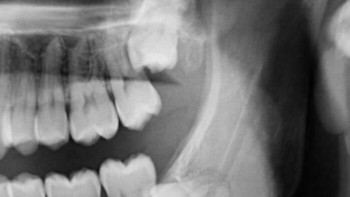

Foto scan CT memperlihatkan kondisi rahang yang dimakan tumor. Foto: Boredpanda